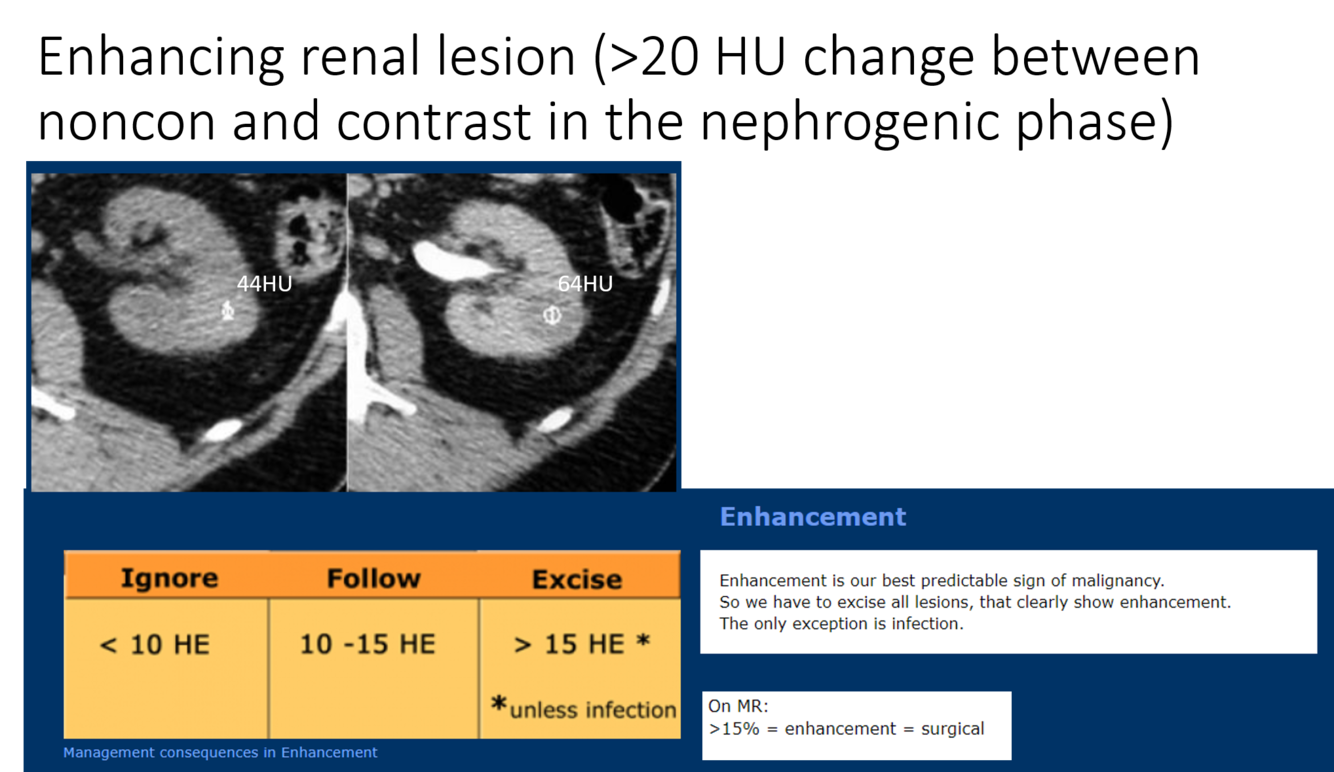

is this mass enhancing?

yes!

new finding. Management?

excise it